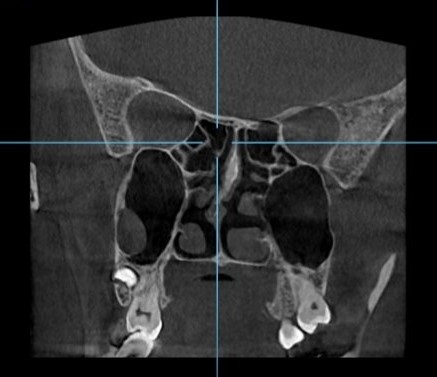

• Ứng dụng CBCT  khảo sát xoang

Hình ảnh CBCT cho phép nha sĩ quan sát rõ ràng các xoang mũi, đặc biệt là xoang hàm trên - xoang lớn nhất và có liên quan trực tiếp đến vùng răng hàm trên. Trong điều kiện bình thường, xoang sẽ xuất hiện dưới dạng các vùng tối trên phim. Tuy nhiên, khi có các vấn đề về xoang như viêm, dị ứng, u nang... các vùng này sẽ xuất hiện những thay đổi về mật độ, giúp nha sĩ phát hiện sớm các bệnh lý.

Ngoài viêm xoang, CBCT còn giúp phát hiện các bệnh lý khác như u nang xoang hàm, vách ngăn xoang. U nang xoang thường xuất hiện dưới dạng một khối tròn hoặc bầu dục, có viền rõ ràng. Vách ngăn xoang là một vách xương chia xoang thành hai phần, nếu vách ngăn quá dày hoặc lệch lạc có thể gây khó khăn cho việc điều trị các bệnh lý về xoang.